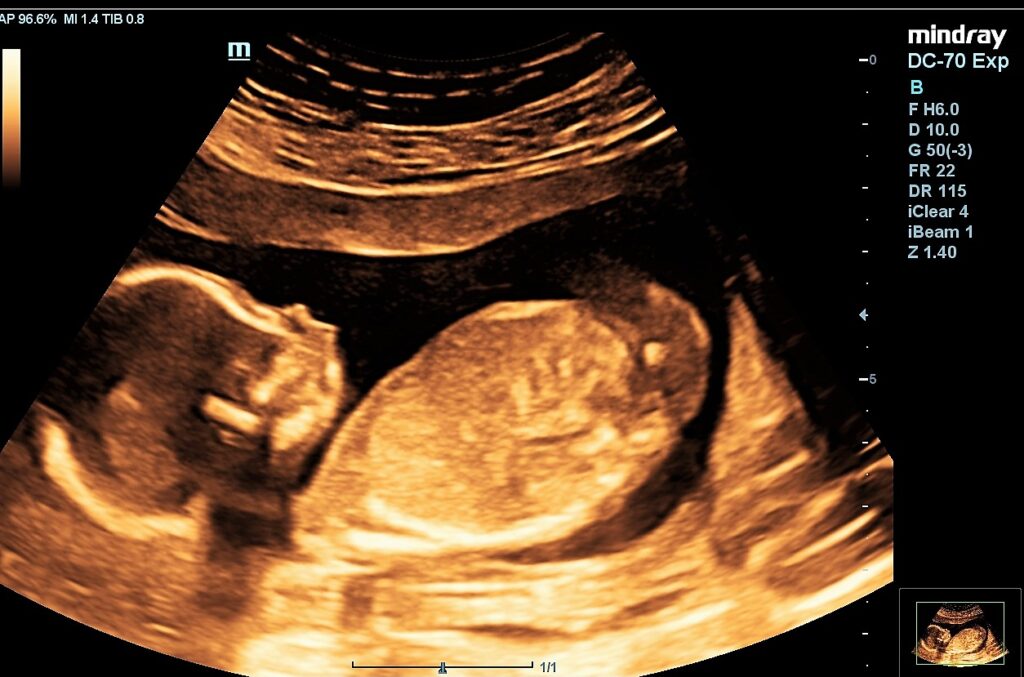

MyBaby 4D Watford kindly gifted us a wellbeing scan during week 17 of our pregnancy so we could check how our baby was growing and whether there were any other issues which needed to be flagged before our 20-week NHS scan. I had been spotting until 13 weeks, so I was very eager to check how my membranes were doing and whether my baby was ok because I hadn’t felt her move yet. I was so glad to see that she was jumping around enjoying herself in my tummy! The heartbeat was clear and the image on the TV was so crisp that we could immediately spot that she was a girl. We could even see the umbilical cord and her drinking!

We weren’t able to get a 3D preview because she wasn’t in the right position, but Saad, the owner of Hey Baby 4d Watford, said that it’s too early for a 4D scan, as babies can look a bit alien-like at 17 weeks, anyway. The best time to have a 4D preview would be at a well-being scan at around 27 or 28 weeks.

Dalson, the licensed sonographer and wife of Saad, managed to get a lovely picture of the baby’s feet and legs, which was beautiful to see. She explained in great detail where each of the organs and limbs was. The membranes outside looked good too, which I was relieved about, as my membranes rupturing was my biggest fear.

The scans were also in sepia rather than the grey you see at the hospital. I found that sepia made it easier to see the baby in detail, and the two printed scans we were provided with showed the clarity of our new baby.